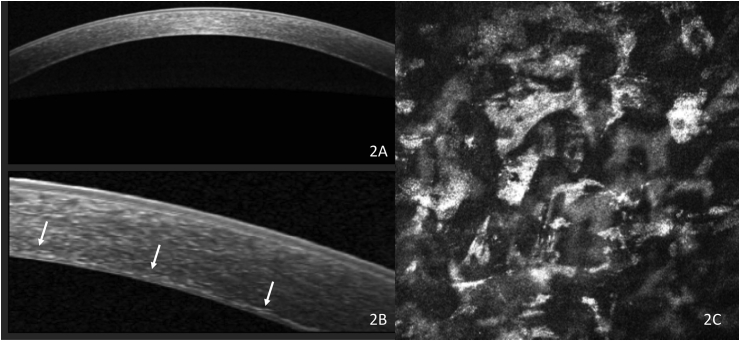

A 55-year-old man with HIV and disseminated MAC on rifabutin therapy for 3 years presented with bilateral diffuse corneal deposits. At the time of presentation, his rifabutin therapy had been discontinued 3 months prior. His best corrected visual acuity was 20/150 in the right eye and 20/200 in the left eye. On examination, he was found to have bilateral, diffuse, fine, pigmented corneal deposits centrally and peripherally presumably in the endothelial layer, bilateral non-visually significant nasal pterygia, and bilateral visually significant cataracts (Fig. 1). There was no evidence of uveitis, anterior lens capsule deposits or retinopathy. Pachymetry was 586um in the right eye and 576um in the left eye. AS-OCT revealed diffuse hyperreflective deposits in the posterior stroma rather than on the endothelium (Fig. 2A and B). Confocal microscopy demonstrated hyperreflective polymorphous deposits in the deep stroma, but none in the endothelium. (Fig. 2C).

Fig. 2.

Anterior segment optical coherence tomography scan showing widefield (A) and magnified (B) scan demonstrating hyperreflective deposits in deep stroma (arrows). Confocal microscopy (C) demonstrates hyperreflective deposits admixed with keratinocytes in deep stroma.